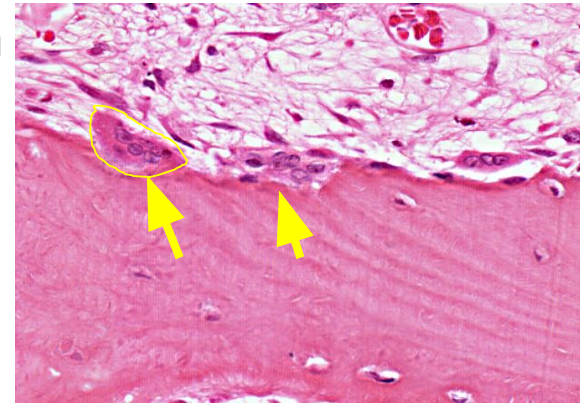

What is the function of osteoclasts?

Large multinucleated cells that resorb bone by secreting acids and collagenases. Located at the edge of bone matrix